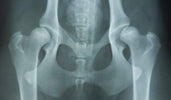

Heupdysplasie is een erfelijke aandoening waarbij de heupkom en de heupkop niet goed op elkaar aansluiten. Dit zorgt voor een instabiel gewricht dat na verloop van tijd slijtage en pijn kan veroorzaken. Hoewel het vooral voorkomt bij grote hondenrassen zoals de Duitse Herder, Labrador Retriever en Golden Retriever, kunnen ook kleinere hondenrassen ermee te maken krijgen.

Foto van: licg